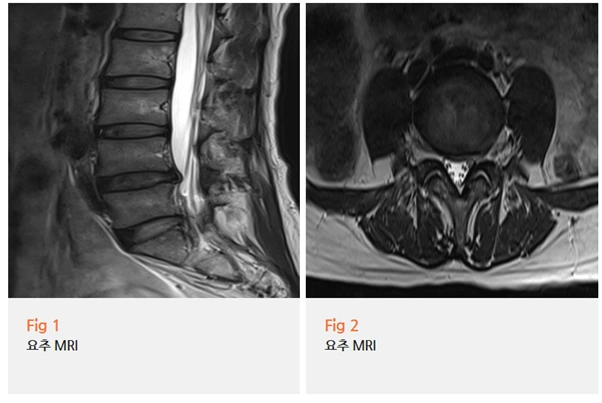

검사 결과가 나왔을 때, 환자분도 깜짝 놀라셨습니다.

요추 추간판 탈출증 소견이 확인됐고,

하지 근전도 검사에서는 만성 요추 신경근병증 소견까지 함께 나왔어요.

고관절 MRI에서는 고관절 자체에는 구조적 문제가 없었고요.

한 달 내내 고관절이 아프다고 생각하셨던 통증이, 사실은 허리에서 내려오는 신경 압박이 원인이었던 거예요.